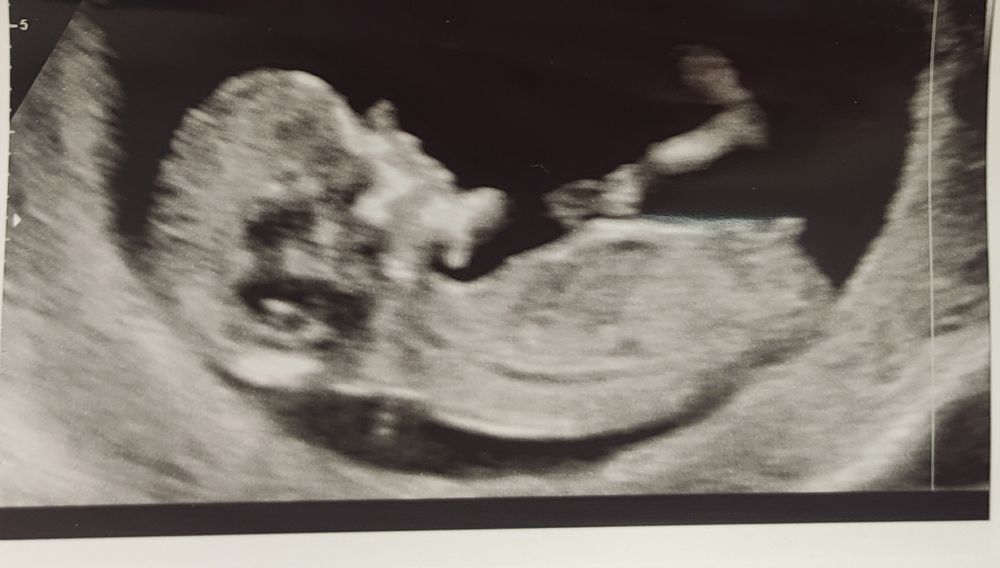

Подскажите девочки сделали УЗИ и хотим узнать этот отросточек похож на девочку?Но по ощущениям всегда думала что мальчик

Вроде бугорок параллельно идёт,значит женский пол.но меня лично мои ощущения с момента // про пол не подводили.